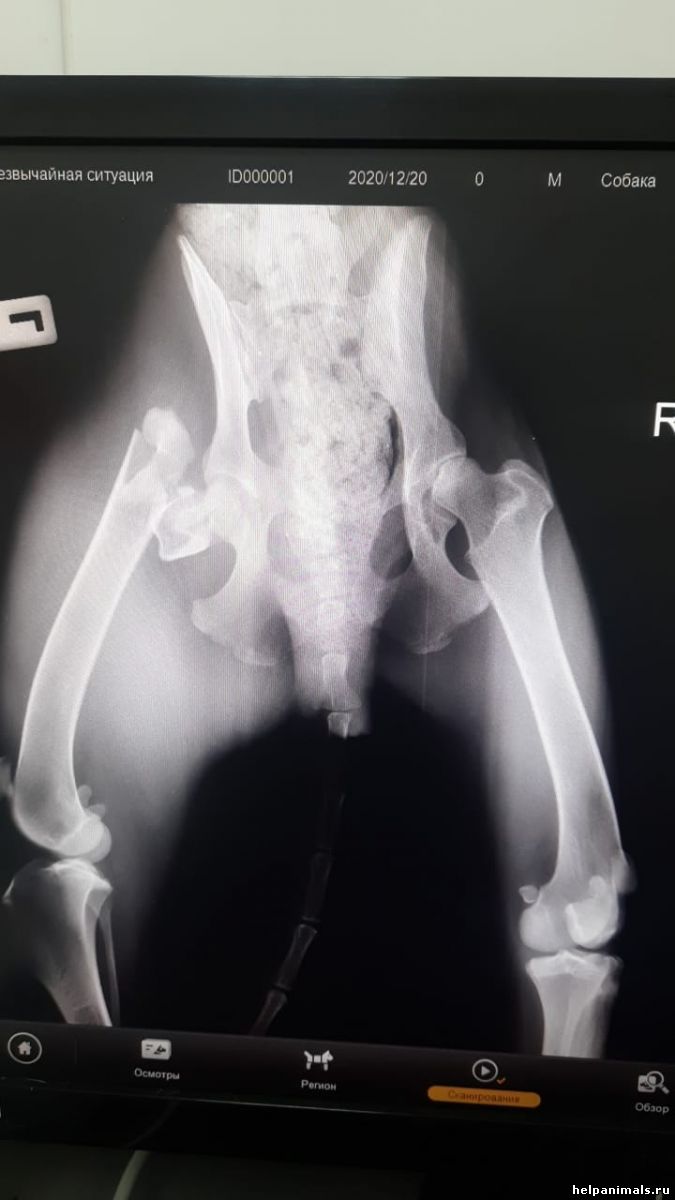

Одри. Перелом двух лап. Автотравма

Диагноз Одри

пневматоракс, открытый перелом передней лапы, перелом бедра, вывих головки бедра правой лапы. Состояние тяжелое. Находится в стационаре Зоодоктора.